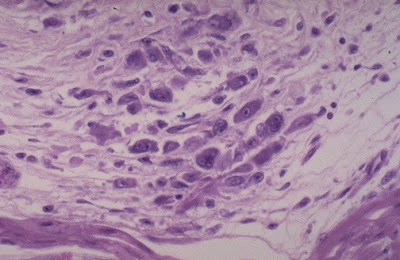

The interstitial lymphocytic infiltrates shown here are characteristic for a viral myocarditis, which is probably the most common type of myocarditis. Many of these cases are probably subclinical. Some may be a cause for sudden death in young persons. There is usually little necrosis. The most common viral agent is Coxsackie B.